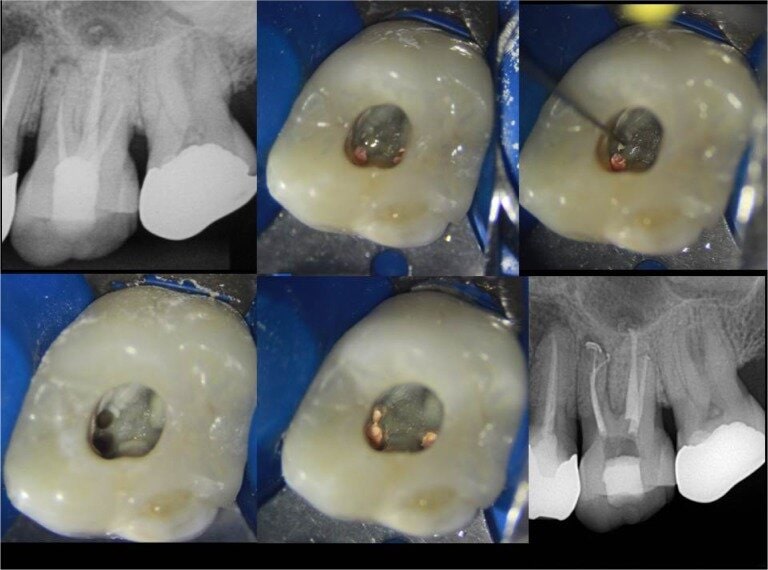

Tehnike pronalaska sekundarnog meziobukalnog kanala

Oblik obrisa pristupnog kaviteta prvog gornjeg kutnjaka trokutast je i smješten u mezijalnoj polovici zuba s osnovom prema bukalno i vrhom prema lingvalno (Slika 3.). Meziobukalni korijen vrlo je širok u bukolingvalnom smjeru, tako da je česta pojava manjeg sekundarnog meziobukalnog kanala. [8] Dno pulpne komore ima određena morfološka obilježja koja su od velike pomoći pri traženju kanala. Obično su na dnu vidljive linije koje vode prema ulazima u kanale i tvore zamišljenu „mapu“, odnosno rostrum canalis. [1] Primarni meziobukalni kanal smješten je blago distalno u odnosu na vrh meziobukalne kvržice, dok je manji sekundarni meziobukalni kanal smješten mezijalno od zamišljene linije koja povezuje primarni meziobukalni i palatinalni kanal, približno na udaljenosti 1 do 3 mm od primarnog. [4] Sam ulaz u sekundarni meziobukalni kanal teško je uočljiv kliničkom inspekcijom zbog dentinskog ramena koje ga pokriva i koje je potrebno ukloniti za lakši pristup kanalu. Osim dentinskog ramena, problem je i meziobukalni nagib ulaza te nagla zavijenost kanala u koronarnoj trećini prema mezijalno što ukazuje na najjednostavniji pristup iz distopalatinalnog kuta. [10] Upravo iz navedenih razloga, kako bi se poboljšala sama pristupačnost kanalu, potrebna je početna priprema i modifikacija pristupnog kaviteta u romboidni oblik uz oprez i minimalnu invazivnost. Istraživanjem je dokazano da je uklanjanje dentina s dna pulpne komore (tzv. troughing) do 2 mm od palatinalnog prema primarnom meziobukalnom kanalu korisna metoda te da su njezine prednosti nadmašile rizik od perforacije. [1] Potrebna je i dobra vizualizacija dna pulpne komore za što se koristi mikroskop, lupe ili barem intraoralno ogledalo s prednjom reflektirajućom površinom. Uz dobru pristupačnost i vizualizaciju lakše je istraživanje dna pulpne komore i traženje ulaza u kanal. Instrumenti poput DG16 Explorer (Slika 4.) ili tanki instrument poput D finder #10 (Slika 5.) od velikog su značaja za lociranje kanala. Iznimno su korisni i ultrazvučni instrumenti koji selektivno uklanjaju kalcifikacije u pulpi i čuvaju dentin od pretjerane štete te otkrivaju skriveni ulaz u kanal. Važno ih je pažljivo koristiti, laganim, kontroliranim pokretima kako bi se izbjeglo pretjerano uklanjanje dentina i iatrogena perforacija. Kod samog traženja kanala, irigacija može pomoći u njihovoj lokalizaciji. Natrijev hipoklorit ima antimikrobna svojstva, osigurava bolju vidljivost, smanjuje rizik od kontaminacije, omogućuje lakši pristup instrumentima te uklanja ostatke organskog materijala. Pulpni ostaci mogu reagirati s natrijevim hipokloritom pri čemu se stvaraju mjehurići, odnosno dolazi do stvaranja kisika, što je pokazatelj položaja ulaza u kanal te potencijalnog postojanja novih, neotkrivenih kanala. Uz natrijev hipoklorit, kao dijagnostičko sredstvo za lociranje kanala upotrebljava se i kemijski spoj 1% natrijev fluorescein. To je oftalmološka otopina koja ima svojstvo vezanja za vezivno tkivo i svijetli kada se izloži plavom svjetlu. Nalapatti i Glassmann predložili su njegovu upotrebu, na način da se otopina aplicira u pulpnu komoru i ostavi da djeluje i reagira 2 minute. [1] Aplikaciju je potrebno obaviti oprezno i paziti na određeni vremenski interval djelovanja, budući da postoji rizik od obojenja zuba. Nakon toga potrebno ju je izložiti plavom polimerizacijskom svjetlu, a kanale promatrati mikroskopom. Važno je obilno isprati pulpnu komoru natrijevim hipokloritom nakon završenog postupka. Na temelju te tehnike, napravljen je i veliki pomak u razvitku mikroskopa, odnosno kobaltno-plavog filtra koji omogućuje još precizniju i jednostavniju primjenu natrijevog fluoresceina. [1] Još jedan vrijedan dijagnostički alat, koji nam omogućuje trodimenzionalan prikaz anatomije jest CBCT (konusna kompjutorizirana tomografija). Ova tehnologija omogućuje bolju vizualizaciju, prepoznavanje varijacija, planiranje samog pristupa, minimalno invazivnu preparaciju te veću predvidivost terapije (Slika 6.). Kliničkom studijom dokazano je da je učinkovitost korištenja CBCT-a u pronalaženju dodatnih sekundarnih meziobukalnih kanala u maksilarnim kutnjacima ograničena te je sam kanal bio prikazan u 33 % slučajeva. [11]